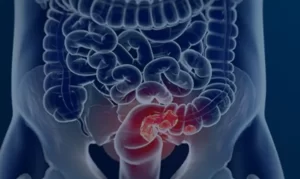

Pacientes com câncer colorretal são diagnosticados em estágio avançado

Demora no diagnóstico reduz de forma acentuada possibilidade de cura Por Alana Gandra, compartilhado da Agência Brasil Lançado nesta

Demora no diagnóstico reduz de forma acentuada possibilidade de cura Por Alana Gandra, compartilhado da Agência Brasil Lançado nesta